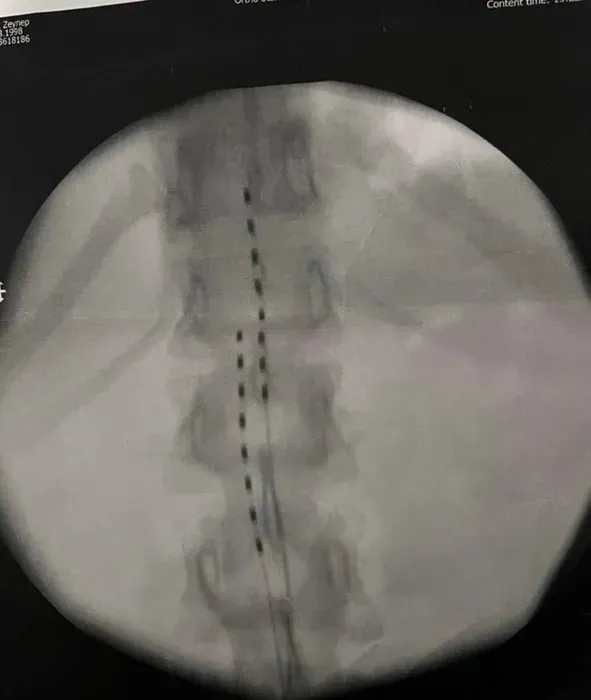

Deri altına koyulması gereken silikon kas altına koyulduğu için iki bacağımda da ağır siyatik hasarından kaynaklı felç geçirdim. 15 gün Cihantimur'un hastanesinde yattım. Daha sonra benim kalçamdaki silikonu çıkardılar. Çünkü hastane raporlarında silikonları takmaya devam edersem hayatımın sonuna kadar felçli bir şekilde hayatıma devam edecektim. Silikonu çıkardıktan sonra beni hastaneden attılar. Hastanede yattığım sürede hukuka aykırı bir şekilde ben ilaçların ve narkozun etkisindeyken evrak imzalattılar. Bu evrak Bülent Cihantimur'dan şikayetçi olmamam, onun adını hiçbir yerde geçirmeyeceğime dair ve hiçbir mahkemeye başvurmamam içinmiş" dedi.